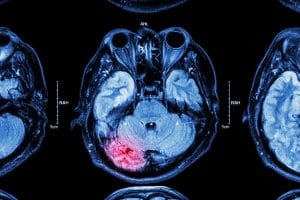

What is a traumatic brain injury?

A traumatic brain injury happens when there is a blow to the head that interrupts normal brain function. More specifically these head injuries can lead to memory problems, blurred vision, muscle weakness, and loss of consciousness. A mild traumatic brain injury may not leave long-lasting symptoms but a moderate or serious TBI can lead to Pandora’s box of medical problems in the future. Some additional problems you may face after a TBI include: